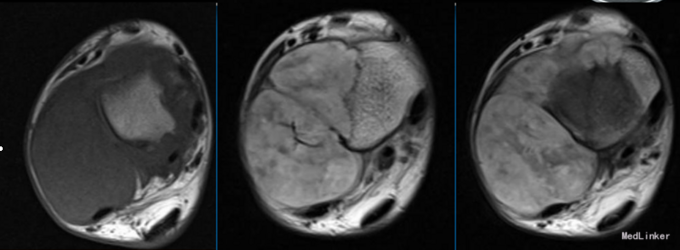

查体:右外踝肿胀,皮肤颜色暗红色,皮温增高,右侧踝可触及质韧肿物,基地广泛,移动度差,肿物按压有轻度胀痛,无叩痛。 辅查:右胫腓骨X线片示:右胫腓骨远端骨质缺失,周围软组织肿胀,不除外骨肿瘤,建议进一步检查。行MRI示:右胫腓骨远端肿物,考虑恶性肿瘤。实验室检查未见明显异常。

入院诊断:右胫腓骨肿物。入院后行穿刺活检,活检病理示:送检组织见成簇大小不等增生的血管,血管间可见增生的纤维母细胞及硬化的胶原,部分似毛细血管,血管内皮细胞增生,少许呈乳头状伴有纤维素渗出,成簇增生的小血管想骨组织内浸润性生长;结合影像学改变考虑侵袭性血管瘤病。患者予唑来膦酸治疗,治疗后骨化明显,右踝关节胀痛明显缓解。